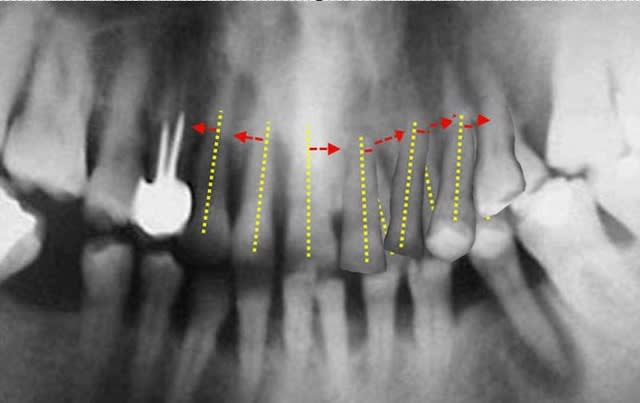

simulation

sur Rx. du résultat du déplacement de 21/22/23/24 autour des apex

le résultat peut être amélioré en cas de béance,

courtoisement

Bjc.